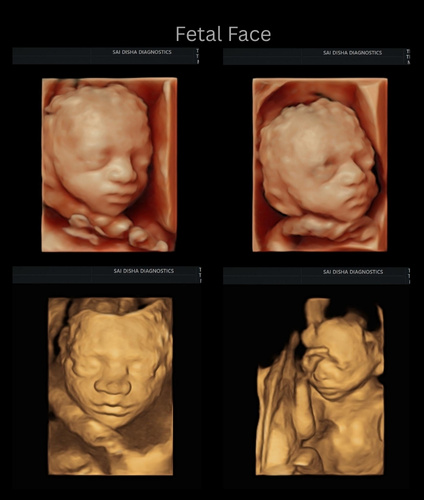

An ultrasound scan, also known as sonography, is a safe and non-invasive diagnostic procedure that uses sound waves to produce real-time images of the inside of the body. Unlike X-rays or CT scans, ultrasound does not use any radiation, making it especially suitable for monitoring pregnancies and for routine diagnostic imaging. During the procedure, a special gel is applied to the skin, and a device called a transducer is gently moved over the area of interest. The sound waves travel into the body and bounce back to create clear images of organs, tissues, and blood flow and fetus inside pregant mother.

Sai Disha Diagnostics offers high-resolution ultrasound imaging to support early and precise diagnosis across a wide range of medical conditions.